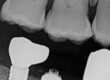

Preop radiograph from the general dentist. We do not have the exact date for this image, but I believe it was taken prior to any recovery attempts. Note the fragment position is above the first implant thread, as viewed in the right cropped image. Green arrow is the top of the implant threading, the yellow arrow is the top of the screw fragment. A Type I or II case in our fractured screw algorithm.